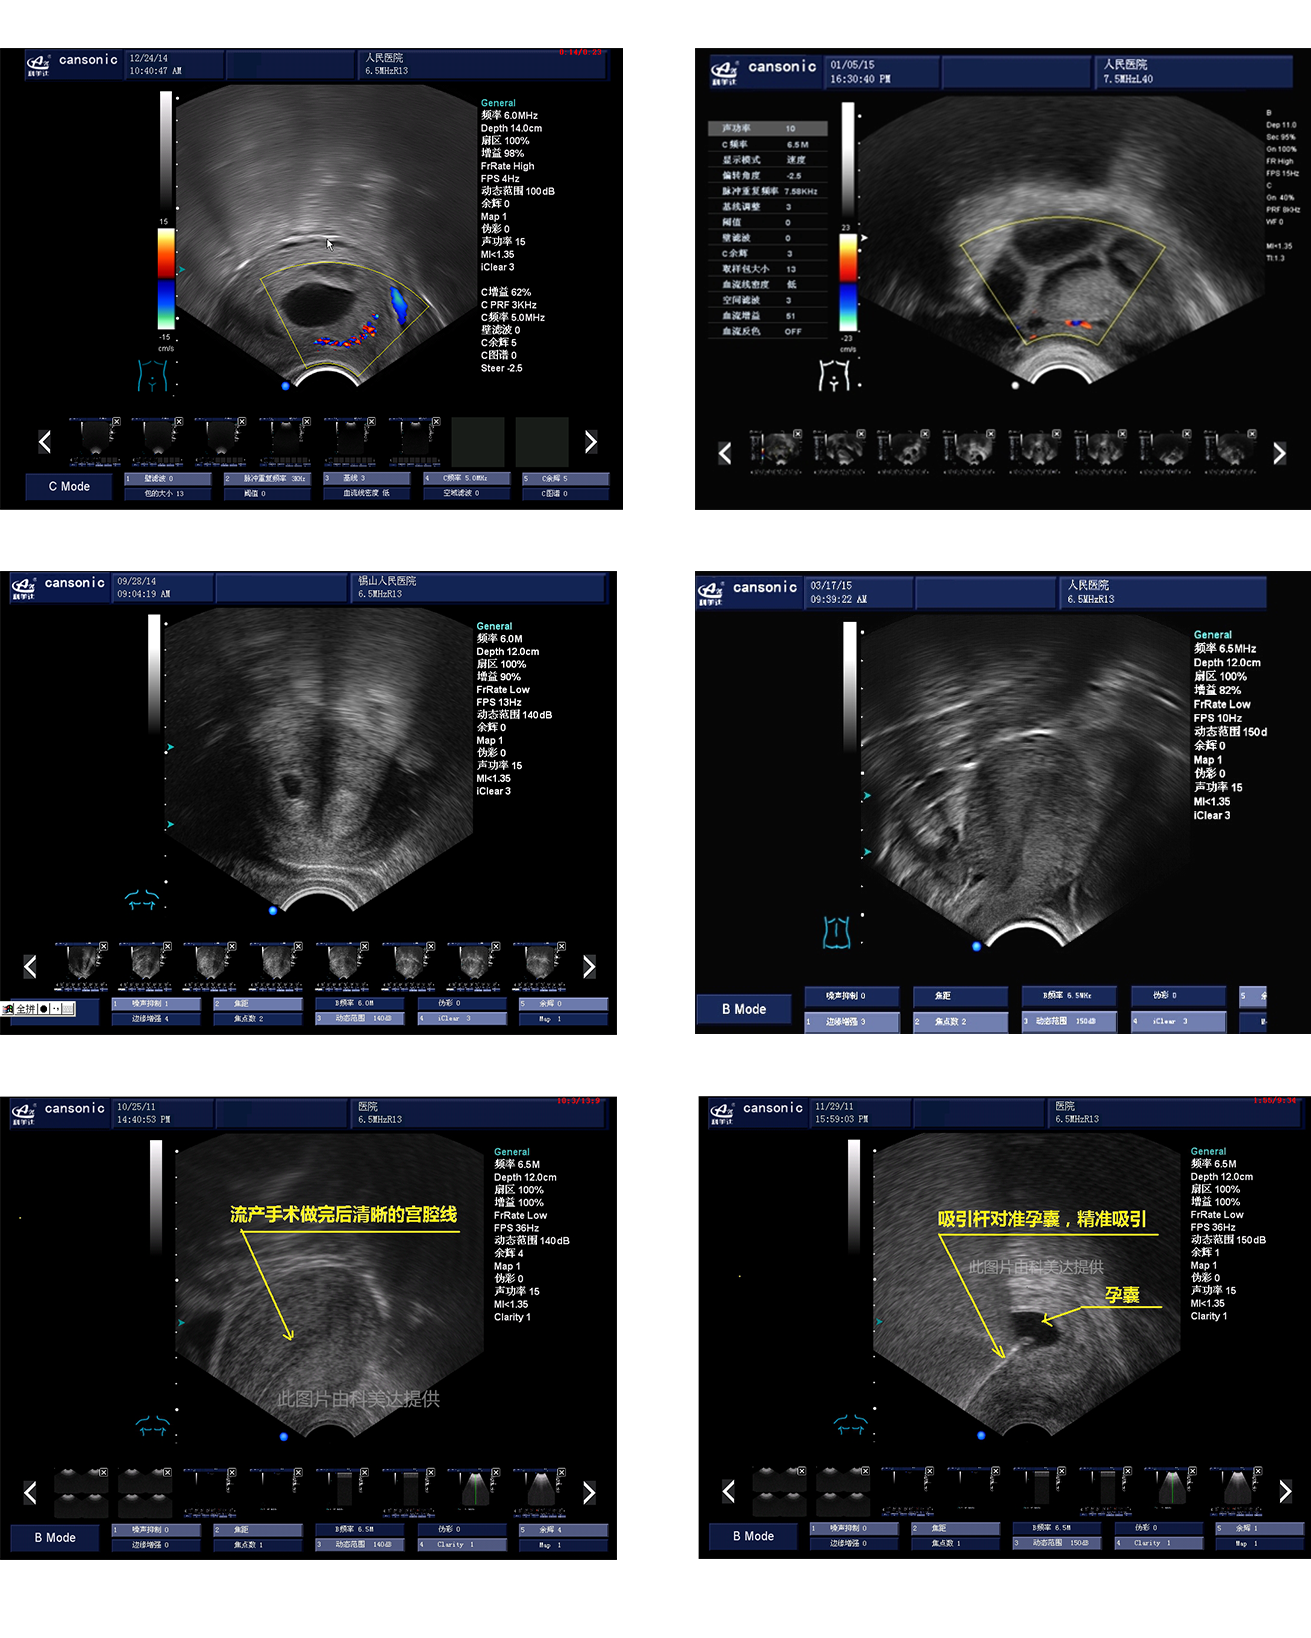

臨床圖示

1、融合業(yè)內(nèi)高端的硬件工藝及智能后處理算法,結(jié)合規(guī)范的操作流程,實現(xiàn)對宮腔手術(shù)的全程監(jiān)測

2、精準(zhǔn)數(shù)字濾波技術(shù),有效降低多普勒噪聲及運(yùn)動偽像,提升血流及多普勒超聲圖像

4、能量多普勒POWER成像模式彩色多普勒Color成像模式

5、血流靈敏度高,清晰可見